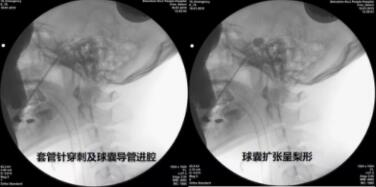

经皮球囊压迫治疗三叉神经痛步骤

2019年01月18日上午,蔡晓东团队在三叉神经痛专家付友增教授(已完成三叉神经半月节阻滞术上千例)指导下于顺利完成了ROSA机器人辅助下经皮穿刺三叉神经半月节微球囊压迫手术(PBC),术中球囊充盈呈标准梨形,球囊充盈体积为0.6ml,压迫时间为90秒。手术过程顺利,从右侧面部皮肤穿刺进针,到穿刺卵圆孔到位,到最后球囊压迫,只需10余分钟便完成手术。